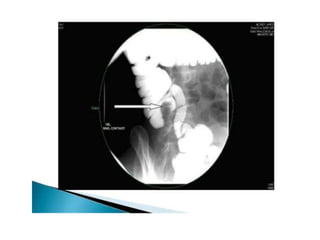

• 32.

OTHER SIGNS- • Conicalcaecum- shrunken in size and pulled out of the iliac fossa due to contraction and fibrosis of the mesocolon. The hepatic flexure may also be pulled down. • Early involvement of the ileocaecal region manifesting as spasm and oedema of the ileocaecal valve. Thickening of the lips of the ileocaecal valve and/or wide gaping of the valve with narrowing of the terminal ileum (“Fleischner” or “inverted umbrella sign”) are characteristic.

• 33.

• “String sign”– persistant narrow stream of barium indicating stenosis. • Purse string stenosis– localized stenosis opposite the ileocaecal valve with a rounded off smooth caecum and a dilated terminal ileum.